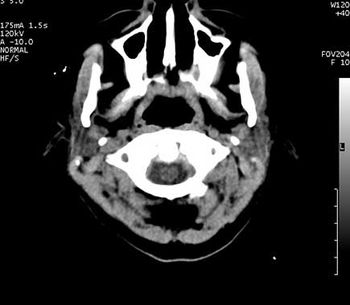

Brain Abscess

Case History: 50-year-old woman with onset of fever and altered mental status.